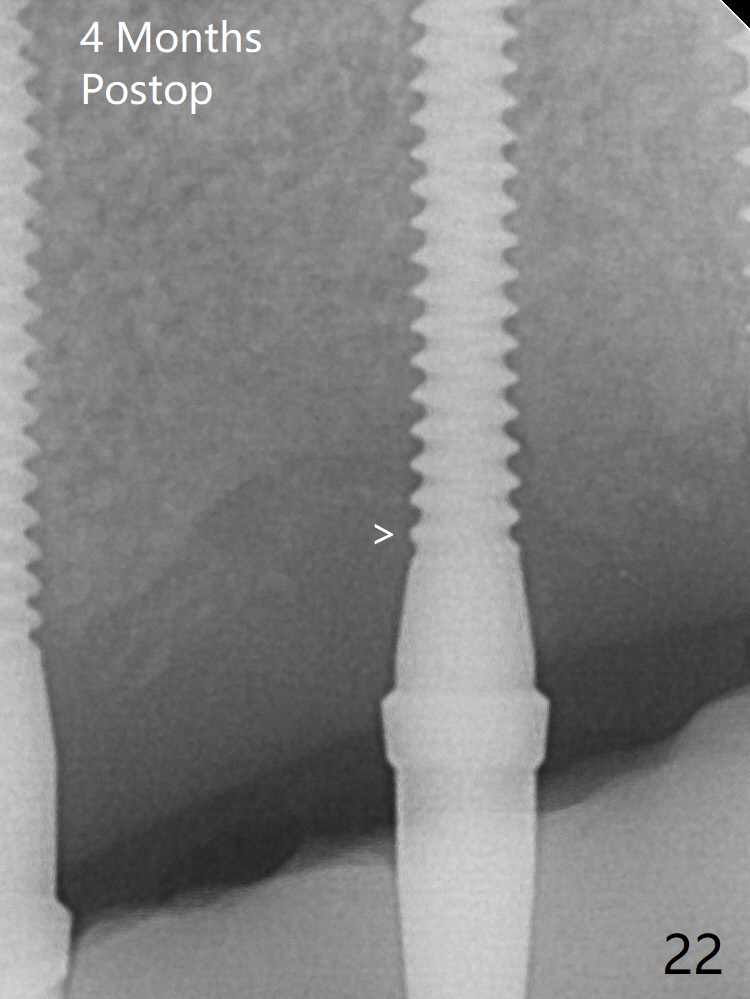

A 2x14(2) mm 1-piece implant is placed at #10 site after change in osteotomy position (Fig.9 arrow), which leaves a concavity mesial to #10 two and a half years later (Fig.22, 42) with 2-3 thread exposure. It would be ideal to place an implant with 4 mm cuff deeper by 2 mm.